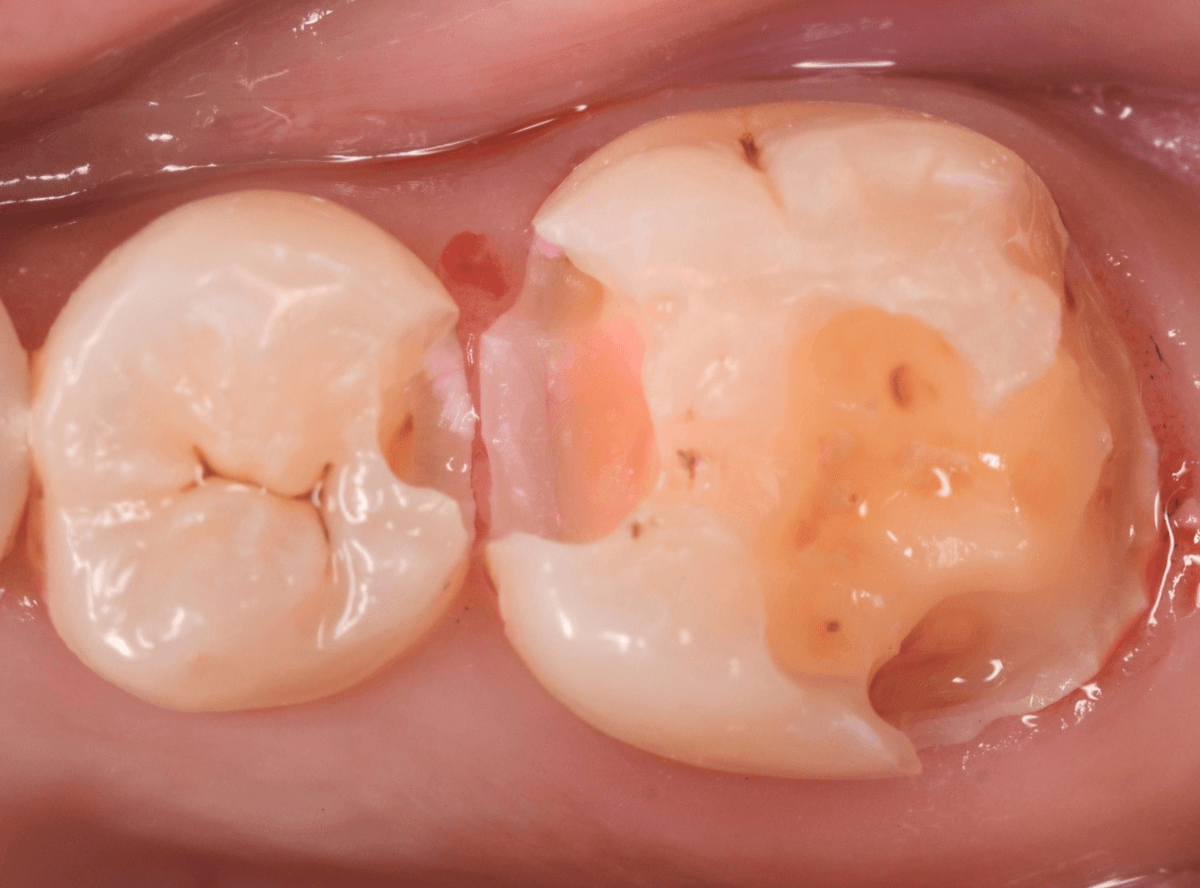

Case.23 歯のすきまから両側が大きな虫歯

「下の奥歯が痛む」という訴えで来院された患者さんのケースです。

目視でも、手前の奥歯がかけていて、中で虫歯が広がってるであろうことは予想できます。

レジンを外して、う蝕検知液で確認します。

レジンの中で虫歯が進行していたのがわかります。

慎重に全ての虫歯を除去しました。

何とか、神経が露出せずに済んでいます。

お薬をつめて、セメントで蓋をして経過観察します。